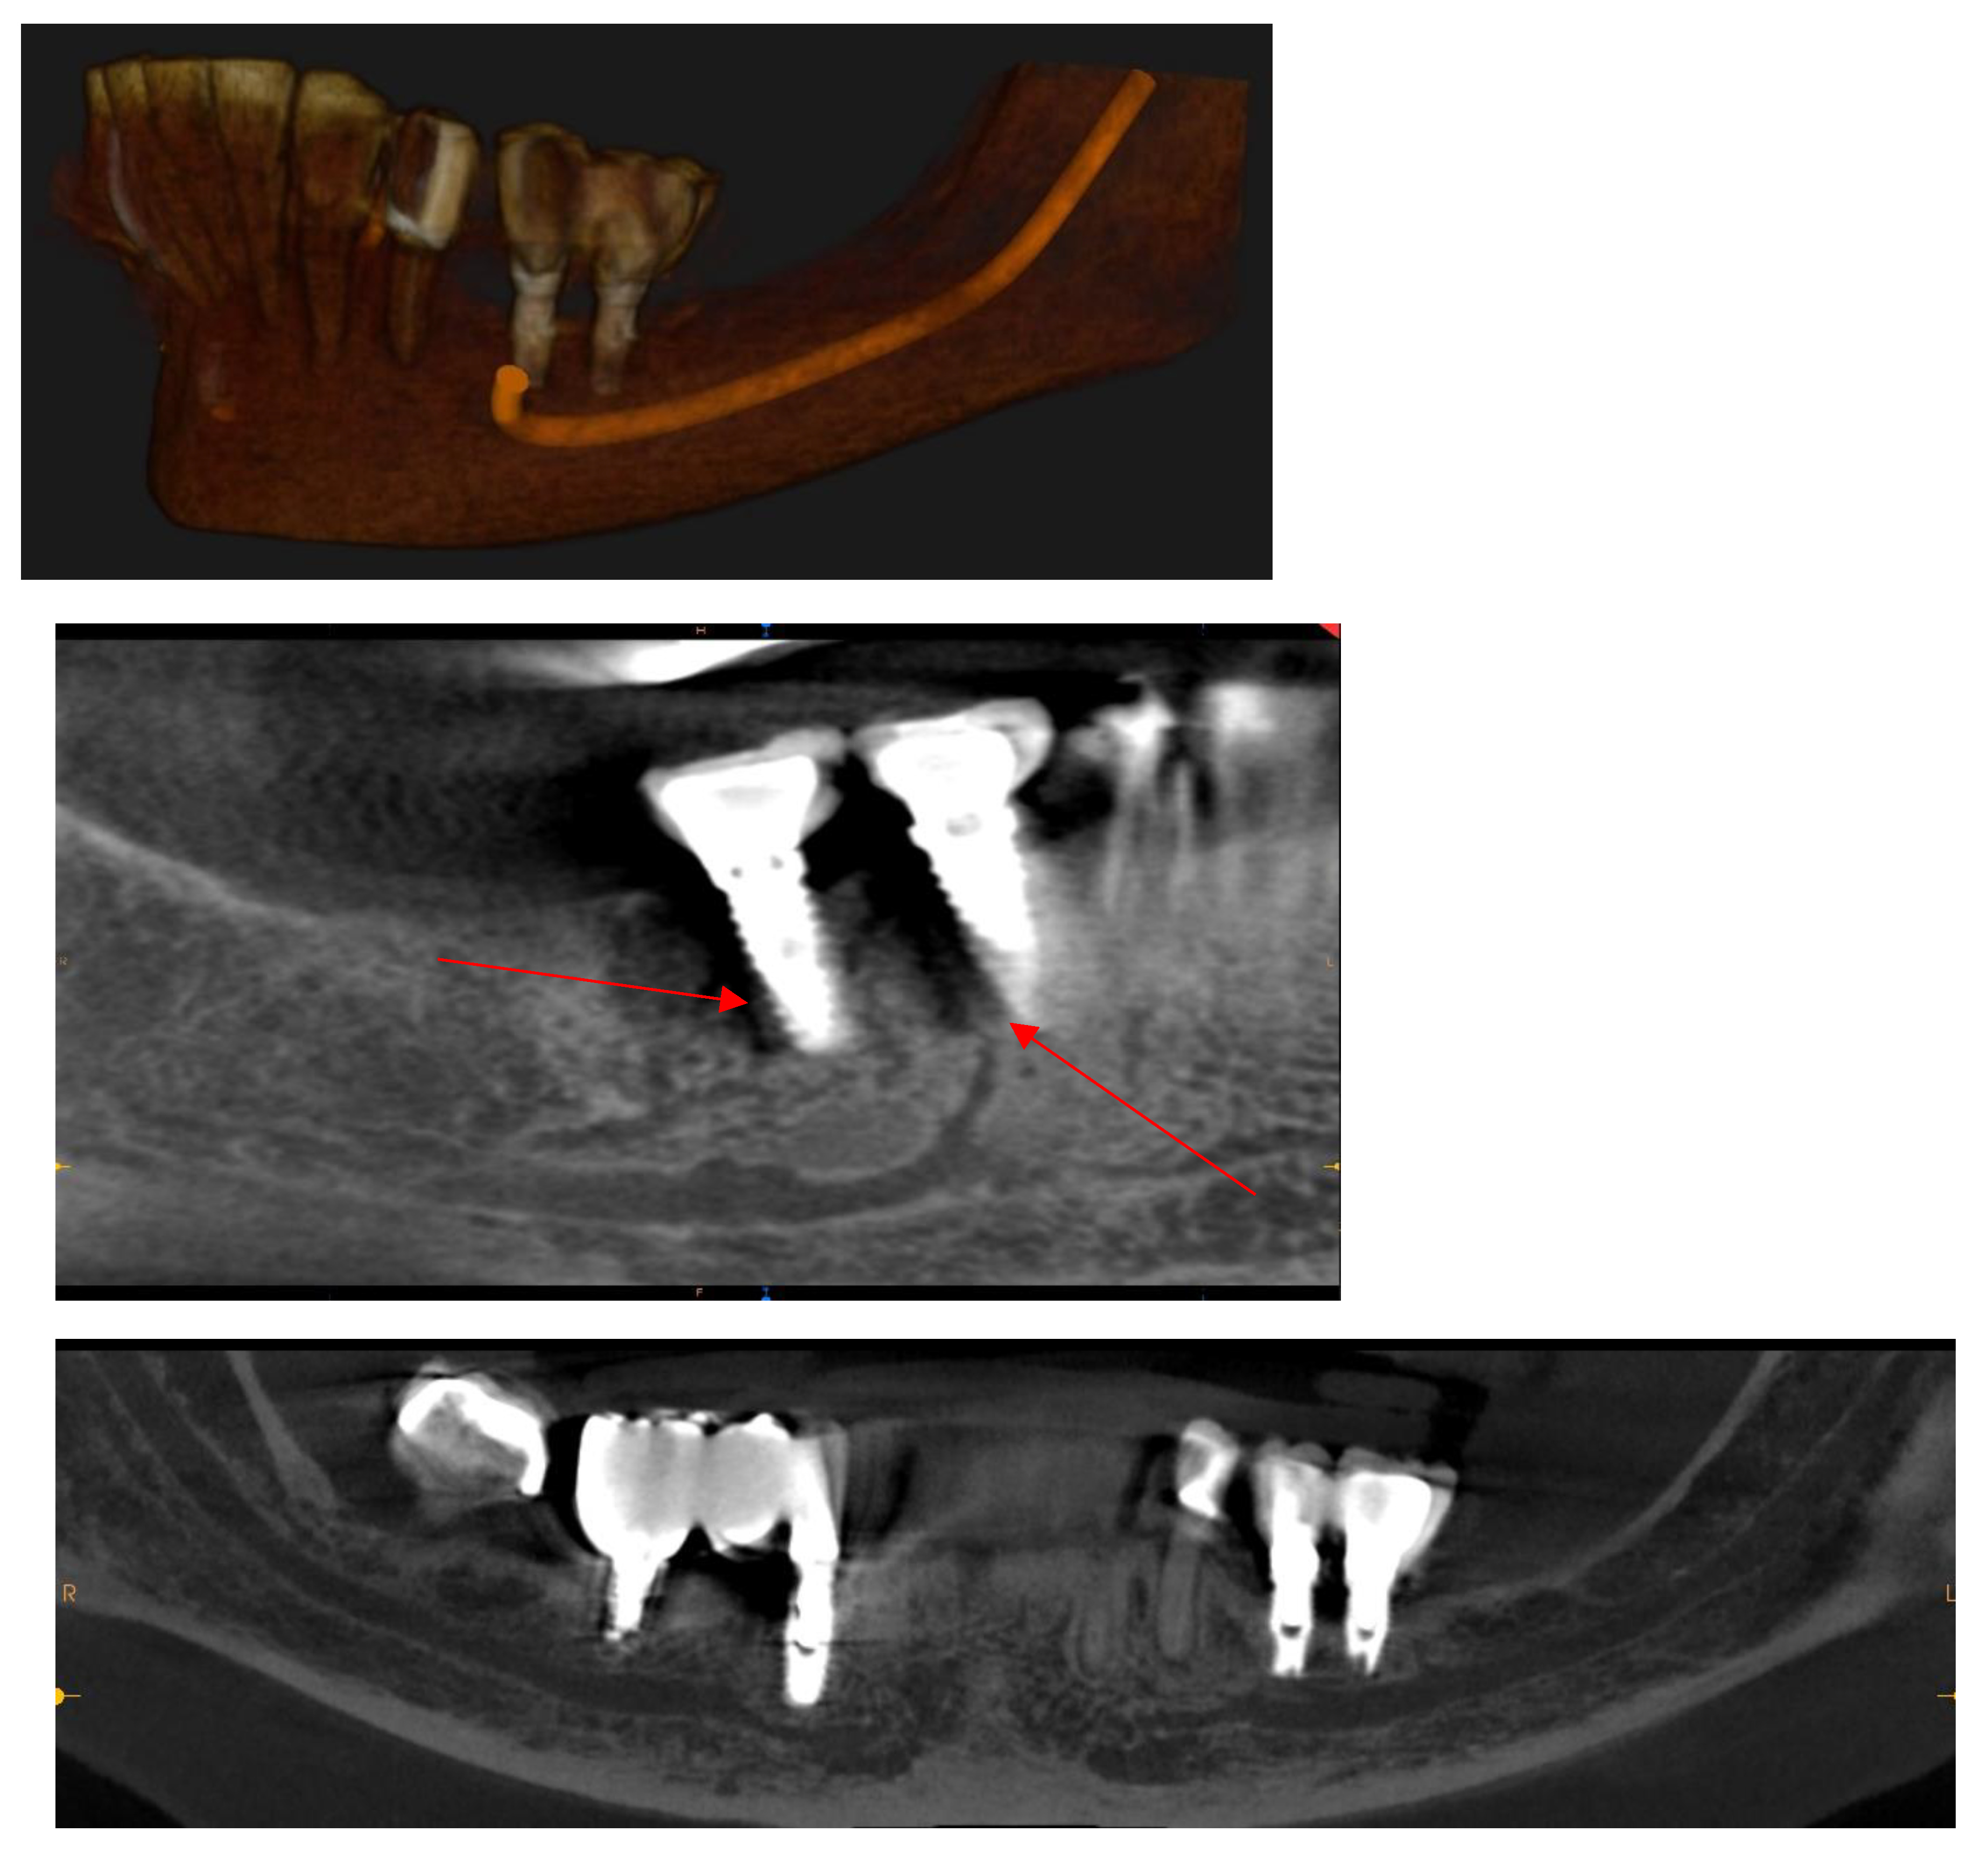

Mandibular Canal

Assessment, Planning and Prevention in the Surgical Context

CBCT in the Post-Surgical Phase: Assessment of Bone Loss and Post-Operative Surgical Complications